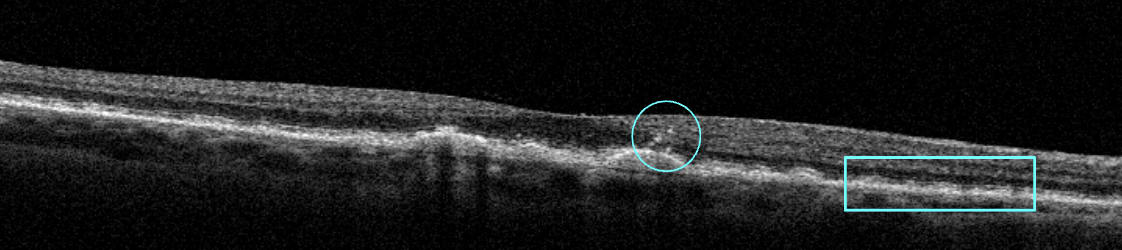

OCT can also identify the earliest signs of GA formation. Incomplete RPE and outer retina atrophy (iRORA) is identified on OCT when hypertransmission defects are seen beneath an area of RPE attenuation that is accompanied by photoreceptor degeneration in the outer retina. Other findings of iRORA also include loss of the external limiting membrane; disruption of the ellipsoid zone; and a hyporeflective, wedge-shaped band in the outer plexiform layer (see Figure 3). The Classification of Atrophy Meetings (CAM) group has identified iRORA as “nascent GA”—a signal that the progression to GA has begun.1